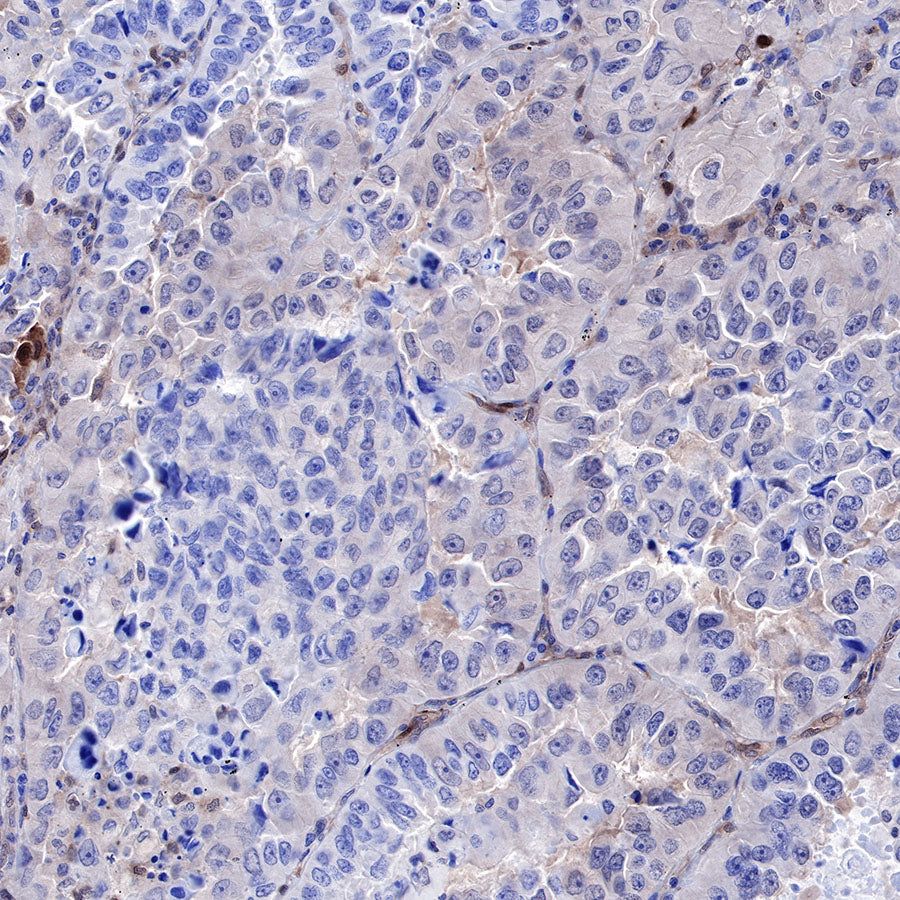

Immunohistochemistry

IHC shows positive staining in paraffin-embedded human lung cancer. Anti-PTEN antibody was used at 1/500 dilution, followed by a HRP Polymer for Mouse & Rabbit IgG (ready to use). Counterstained with hematoxylin. Heat mediated antigen retrieval with Tris/EDTA buffer pH9.0 was performed before commencing with IHC staining protocol.